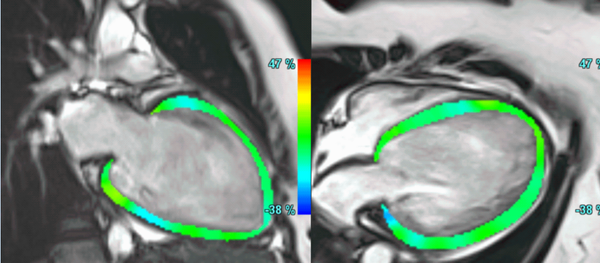

Ischaemic HD

Microvascular dysfunction